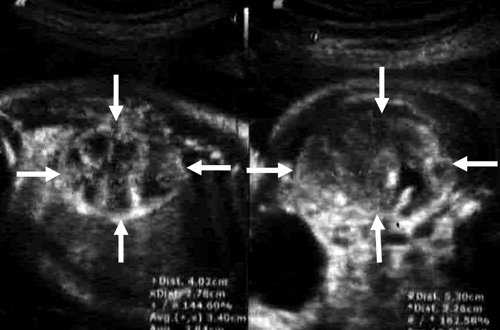

Результаты исследования: размеры плода пропорциональные, соответствуют менструальному сроку беременности. При эхокардиографии особенностей строения сердца у плода не выявлено. При оценке органов мочевыделительной системы обнаружено следующее: правая почка плода нормальных размеров и структуры. Левая почка увеличена до размеров 53х38х46 мм при 95-м процентиле нормативных для срока значений 43х24х23 мм [4] (рис. 1). В структуре почки, преимущественно в верхнем и среднем сегментах, определяется округлое образование без четких контуров, средней эхогенности, приблизительные размеры его 50х35х35 мм. При цветовом допплеровском картировании в образовании визуализируется обширная сосудистая сеть. При допплерометрии индексы сосудистой резистентности (рис. 2) в разных участках образования варьируют в широких пределах (от 0,49 до 0,77).

Рис. 1. Почки плода в режиме 2D. Видна разница в эхографической структуре. Границы почек обозначены стрелками.

В представленном клиническом наблюдении диагноз опухоли почки был поставлен нами практически сразу и не вызывал сомнения, поскольку стандартный протокол ультразвукового скринингового исследования во II и III триместрах беременности требует описания почек и мочевого пузыря. Почки оцениваются в поперечном и продольном сечениях с использованием при необходимости цветового допплеровского картирования (рис. 3, а, б). В данном случае почки плода располагались в типичном месте, но обращали на себя внимание значительная разница в размерах и необычная структура одной из почек (см. рис. 1). В 2D режиме границы опухоли четко не визуализировались, но при использовании технологии VCI (объемное контрастное изображение) можно было более точно определить ее контуры (рис. 4).

Рис. 3. Исследование почек.

а) Поперечное сканирование. Переднезадний размер почек обозначен стрелками.